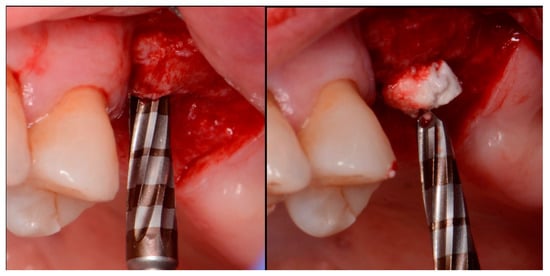

A critical question is about what happens histologically to the graft and at what stage during healing. For example, when delayed socket grafting was performed at a site where a large defect was present following extraction (Figure 18, left), a healing period of 3 weeks post-extraction was needed, allowing primary closure post-graft. This gives us more predictability and simpler surgery, plus two attempts to clean the site. EthOss graft material was placed into the socket (Figure 18, middle) and primary closure with the flap was achieved and secured with sutures (Figure 18, right). Intraoral physical exam and radiographic measurement showed all sites to have regenerated vertically 3–6 mm and horizontally 4–6 mm with new host bone allowing for successful placement of the implants. A core sample was obtained from one case to confirm the series to be in line with earlier findings. Histology was performed by core biopsy at 10 weeks following graft placement and demonstrated well-preserved reactive (woven) trabecular bone with intertrabecular tissue composed of uniformly collagen-rich myofibroblastic tissue and 60% of the core consisting of bone (Figure 19).

Figure 18.

Delayed socket grafting with flap exposure of the site (left), placement of EthOss graft to fill the defect (middle) and flap placement to achieve primary closure (right).